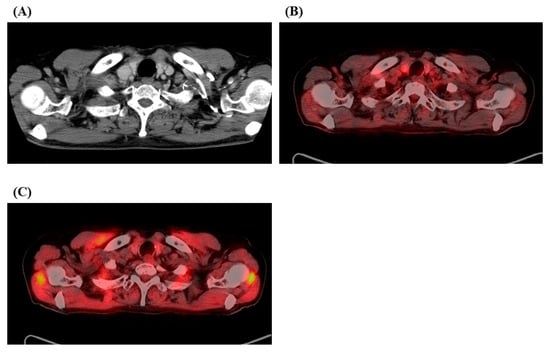

2. Case Report